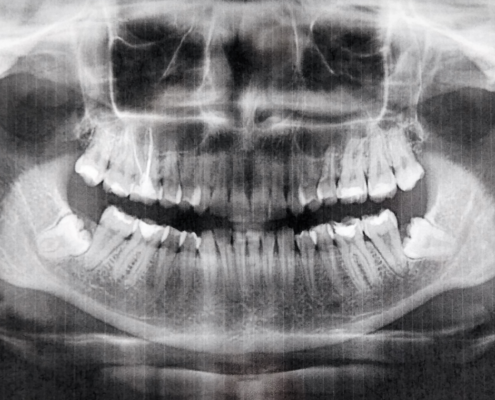

Botox gegen Zähneknirschen

Kann das wirklich helfen?

Wer unter Zähneknirschen leidet, kennt die Folgen: verspannte Kiefer, Kopfschmerzen, abgenutzte Zähne, manchmal sogar Schlafprobleme. Besonders das Zähneknirschen nachts ist tückisch, weil es unbemerkt passiert. Neben Aufbissschienen wird inzwischen auch eine andere Methode diskutiert: Botox gegen Zähneknirschen.

Doch was hat es damit auf sich und für wen kann das sinnvoll sein? Bei MeinZahnarzt Tirol nehmen wir uns Zeit, uns dieser Fragen anzunehmen.